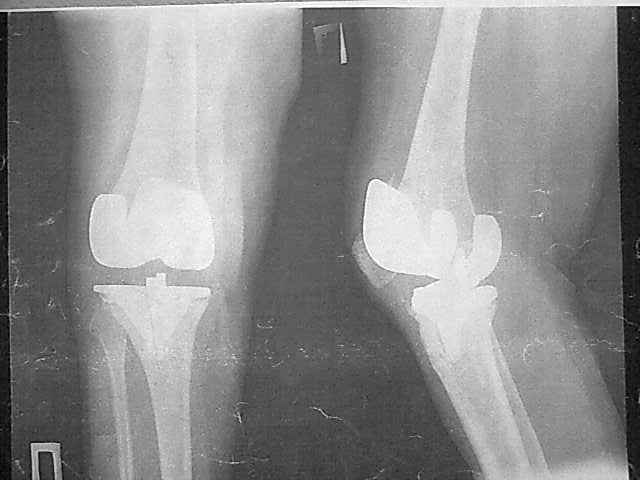

Уважаемые коллеги, прошу Вашего совета по тактике лечения. Женщина 1952 г.р., оперирована в 2006, в одной клинике установлен эндопротез правого коленного сустава, через год нестабильность обоих компонентов, доктор выполняет ревизию обычным протезом с задним стабилизатором. В октябре 2008 - нестабильность, свищ. В другом стационаре все удалено, спейсер с гентамицином, длинный курс антибиотиков. Коллатеральных связок нет. Собственная связка надколенника цела. До удаления протеза - выраженная смешанная контрактура. Сейчас свищей нет, анализы в порядке.

Планы: Стоит выбор 1) Обычный hinge с цементными ножками, вставками под тибиальным и бедренным компонентами с импакционной костной пластикой аллокостью с применением сеток для удержания трансплантата на tibia; 2) Онкологический hinge - с замещением проксимальной голени и сохранением бедра; 3 - артродез.

Александр Николаевич - это просто то, что мы можем сделать исхоя из наличия бесплатных (условно) имплантов и наших навыков работы с ними. Простой hinge - Страйкеровский MRH или онкологический - GMRS, сетки Exchange, артодез - думали над ИМ артродезным гвоздем с аллотрансплантатом. Больная совсем молодая женщина...

Мне очень хотелось узнать мнение коллег на предмет - если ставить простой hinge с костной пластикой - стоит ли использовать только костную крошку или необходим структурный костный аллотрансплантат? Есть ли у кого-то положительный опыт таких операций? Душа у меня не лежит использовать онкологическим протез для голени, т.к. пациентка слишком молода и сохранена собственная связка надколенника.